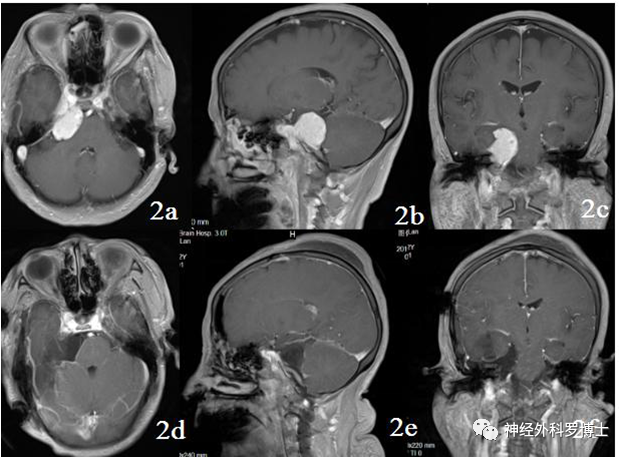

(见下图,上三张为术前,下三张为同一层面术后复查对比,提示肿瘤全切除)

患者48岁女性,以“右侧面部疼痛”为主诉入院。

门诊诊断为三叉神经痛。进了病房后,给予做磁共振检查显示为岩斜区肿瘤。

术前磁共振MRI增强显示中颅窝岩骨尖部和后颅窝(小脑幕下、斜坡)病变,术后1天磁共振复查显示肿瘤全切,无残留,术后患者恢复良好,没有不良症状发生。通过颞下经小脑幕入路一次手术全切病变,避免分期二次手术的痛苦。